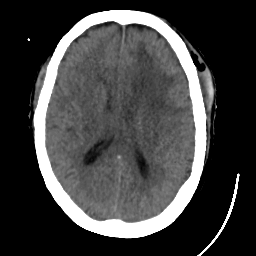

Meningioma: Roentgen-ray CT #1 -- Slice #12

[Home][Help][Clinical] Slice 12